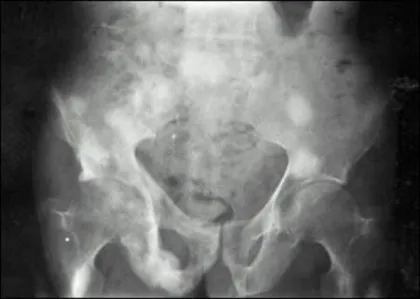

(4) Paget's disease

증상: 뼈 통증, 뼈 변형, 관절염, 신경 압박(청력/시력 문제, 마비 등)이 발생할 수 있으며, 증상이 없을 수도 있다.

특징: 뼈의 파괴와 생성이 비정상적으로 증가하여 정상보다 두껍고 약한 뼈가 만들어진다.파제트 골질환에 걸리면 골조직이 파괴되고 재생되는 과정이 특정 뼈에서 비정상적으로 이루어진다. 몸의 어느 뼈에서도 발생하지만 골반, 쇄골, 척추골, 두개골과 하지뼈에서 흔하다. 병에 걸리면 뼈가 비정상적으로 커지고 구조가 변하며 점차 약화되고 골절이 쉽게 발생한다.

파제트 골질환은 일반적으로 50세 이후에 발생하는데 80세 이상의 사람들에게서도 10명 중 1명꼴로 발생된다. 이 질환은 때로 가족력이 있고 남성이 여성보다 많이 걸린다. 파제트 골질환은 유럽, 북아메리카와 호주에서 가장 흔하고, 아시아와 아프리카에서는 드물다.

진단: X-레이로 뼈 이상을 확인할 수 있다.